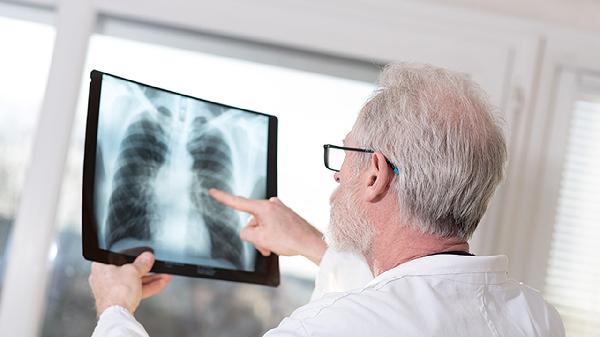

肺结核皮试后无需特殊护理,但应避免使用创可贴覆盖或涂抹药膏。日常注意观察注射部位变化,若出现直径超过15毫米的硬结、水疱或淋巴管炎,提示强阳性反应,需进一步进行胸部影像学检查。结核病确诊需结合临床症状、痰涂片检查和影像学结果综合判断,皮试仅作为筛查手段。